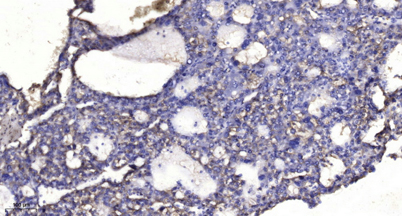

Applications IHC

Recomended Dilution IHC-p 1:50-300